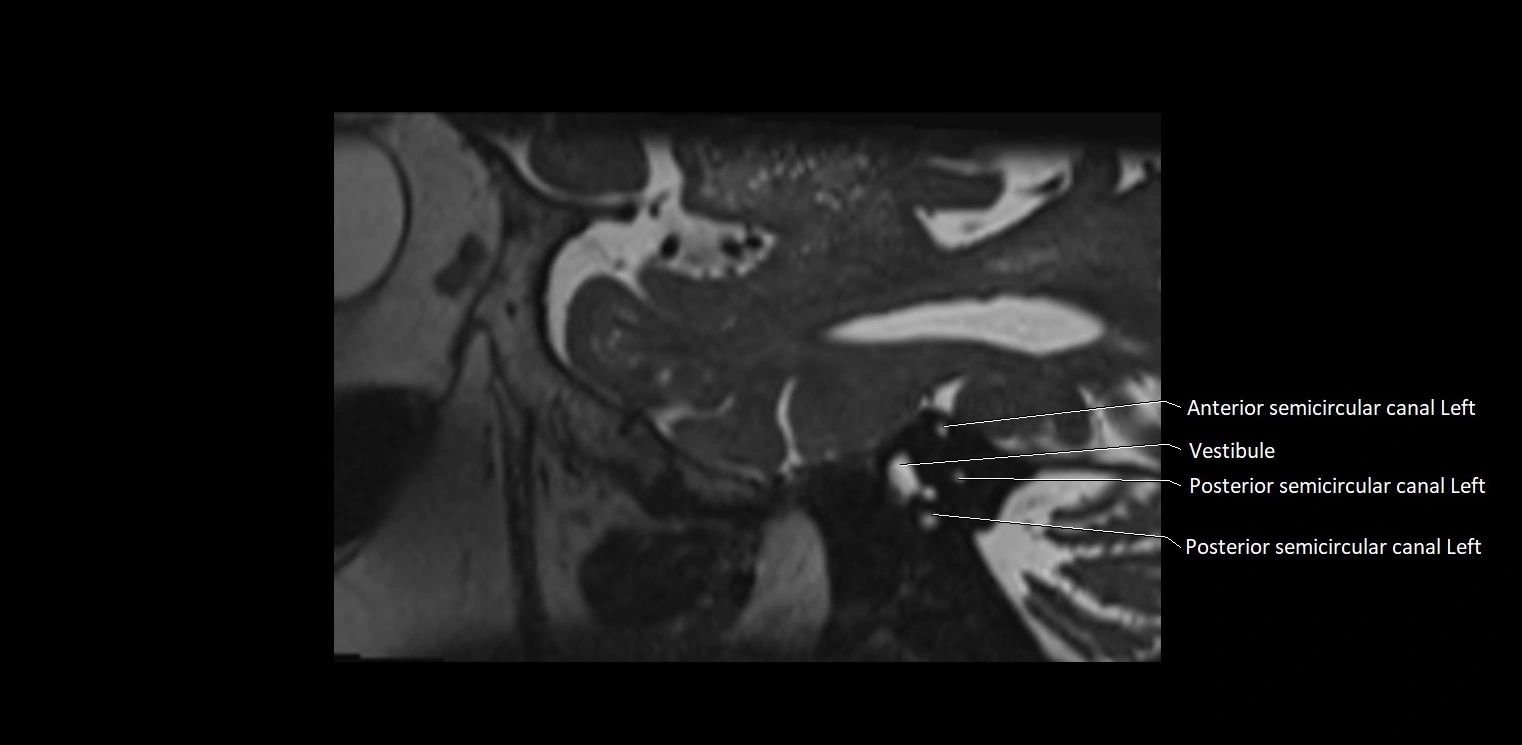

MRI images

image